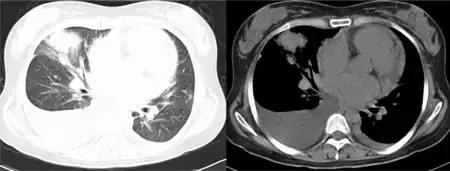

- Radiologic studies show multiple pulmonary infiltrates, with a tendency to central necrosis

Pulmonary infiltration and pleural effusion are usually detected via x-ray.